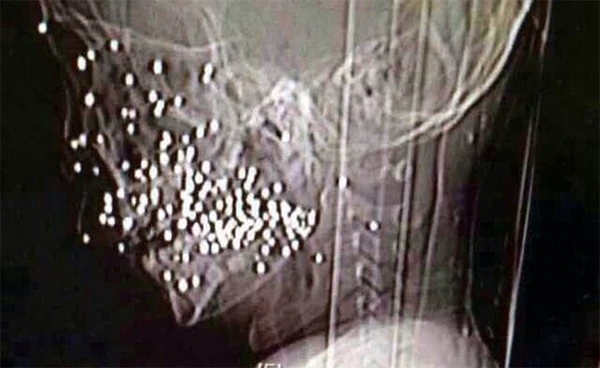

Số đạn được lấy ra sau ca phẫu thuật.

Tại đây, các bác sĩ đã gắp bỏ tổng cộng 86 viên đạn găm ở mặt cậu bé và phẫu thuật chỉnh sửa lại xương ổ răng bị vỡ. Hiện cậu bé đang trong quá trình ổn định nhưng vẫn cần phải tiếp tục điều trị trong thời gian sắp tới.

Bác sĩ Xie Ting, Bệnh viện Nhân dân số 9 Thượng Hải cho biết, loại súng mà cậu bé nghịch là một dạng súng tự chế, thường được nông dân sử dụng để săn thỏ.